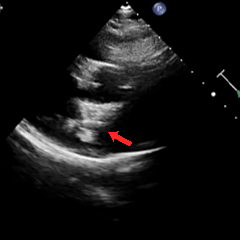

术后1周随访

术后1周复查心脏彩超提示可降解封堵器形态位置良好,无残余分流,周围其他结构无异常。